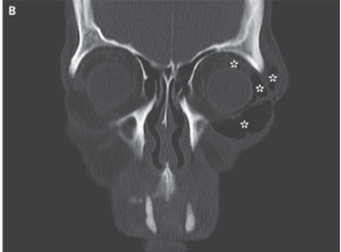

CT施行。眼窩周囲皮下と左眼球後気腫、眼窩下縁骨折を認めたが、眼球は無事だった。

以上より「外傷性眼窩気腫症」と診断された。